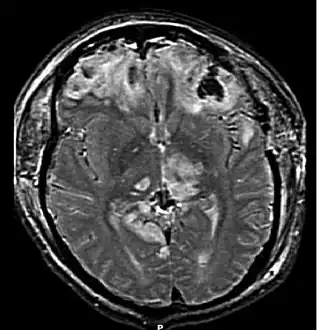

MRI scan showing damage due to brain herniation after TBI[2]

A large percentage of the people killed by brain trauma do not die right away but rather days to weeks after the event;[71] rather than improving after being hospitalized, some 40% of TBI patients deteriorate.[72] Primary brain injury (the damage that occurs at the moment of trauma when tissues and blood vessels are stretched, compressed, and torn) is not adequate to explain this deterioration; rather, it is caused by secondary injury, a complex set of cellular processes and biochemical cascades that occur in the minutes to days following the trauma.[73] These secondary processes can dramatically worsen the damage caused by primary injury[61] and account for the greatest number of TBI deaths occurring in hospitals.[9]

Secondary injury events include damage to the blood–brain barrier, release of factors that cause inflammation, free radical overload, excessive release of the neurotransmitter glutamate (excitotoxicity), influx of calcium and sodium ions into neurons, and dysfunction of mitochondria.[61] Injured axons in the brain's white matter may separate from their cell bodies as a result of secondary injury,[61] potentially killing those neurons. Other factors in secondary injury are changes in the blood flow to the brain; ischemia (insufficient blood flow); cerebral hypoxia (insufficient oxygen in the brain); cerebral edema (swelling of the brain); and raised intracranial pressure (the pressure within the skull).[74] Intracranial pressure may rise due to swelling or a mass effect from a lesion, such as a hemorrhage.[23] As a result, cerebral perfusion pressure (the pressure of blood flow in the brain) is reduced; ischemia results.[9][75] When the pressure within the skull rises too high, it can cause brain death or brain herniation, in which parts of the brain are squeezed by structures in the skull.[23]